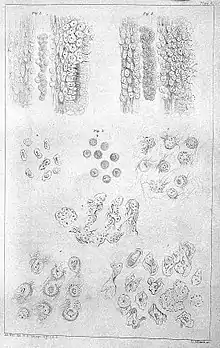

Professor Richard Hill Norris FRSE FRSGS (1830-1916) was a British physiologist, spiritualist and photographer.[1] From the 1880s he began microscopic photography of blood corpuscles and was a pioneer of microphotography. In 1856 he invented the dry collodion photographic plate.[2]

Norris studied medicine at the University of Edinburgh, developing an early interest in microphotography; mainly taking pictures of frogs' blood. In 1856 he invented the first dry collodion photographic plate, during 1858 founding the Patent Dry Collodion Plate Company in Birmingham - one of the first commercial producers of photographic materials in the world.[2]

- On Stasis of Blood and Exudation (1862)

- On the Laws and Principles Concerned in the Aggregation of Blood Corpuscles (1869)

- On the Extrusion of the Morphological Elements of the Blood (1871)

- On the Physical Principles Concerned in the Passage of Blood Corpuscles through the Walls of the Vessels (1871)

- The Physiology and Pathology of the Blood (1882)